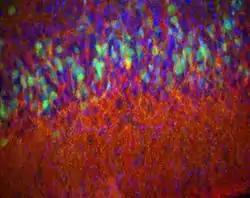

![]() Córtex piriforme de um rato D2-eGFP (verde) de 14 dias com corante manchado para encefalina (vermelho) e DAPI (azul) para mostrar núcleos. Epifluorescência. | |